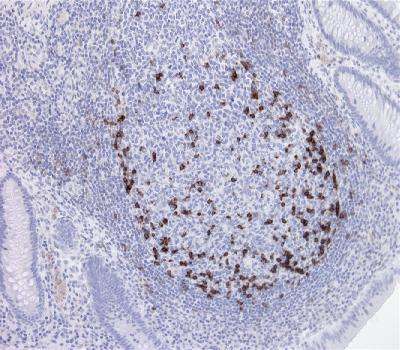

Figure-1: Immunohistochemical analysis of PD1 (Clone: BSR1) antibody on appendix x200 using 1:200 dilution.

Immunohistochemical Analysis :-1:200